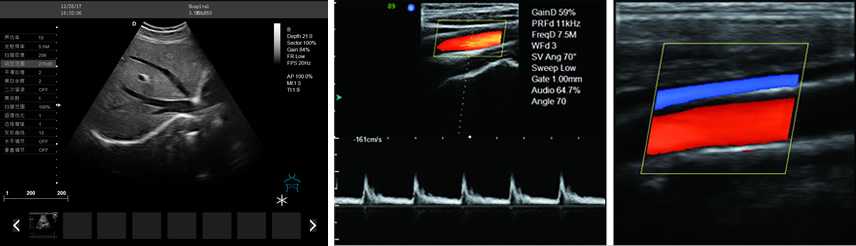

DW-PF522

彩色多普勒

產(chǎn)品性能:高集成數(shù)字式彩色多普勒技術(shù),寬頻探頭,強勁的組合式模塊化軟件設(shè)計,全數(shù)字式大容量圖像存貯和文件歸檔管理,適用范圍:用于人體超聲診斷檢查。